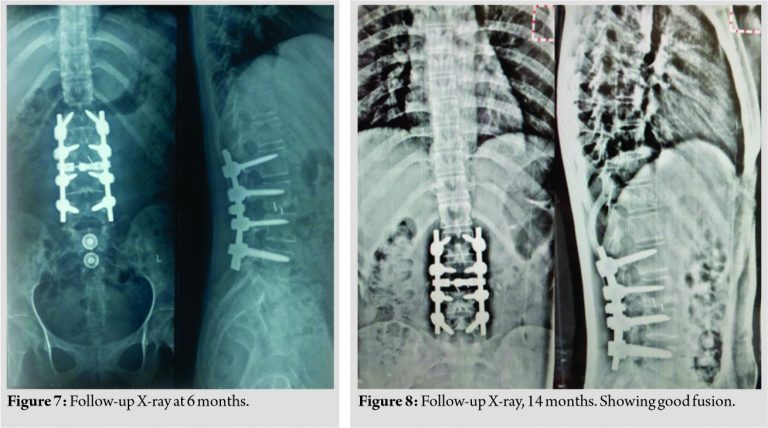

Extensive physiotherapy and passive range of movements of lower limbs were started immediately in the post-operative period. An ankle-foot orthosis was given to prevent equinus deformity at the ankle. The patient was subjected to 23 cycles of intensity-modulated radiotherapy and is symptom- free with good fusion at the latest follow- up (14 months) (Fig. 7, 8). Sensory disturbances recovered completely. (Table 2) shows neurological examination finding at latest follow-up.